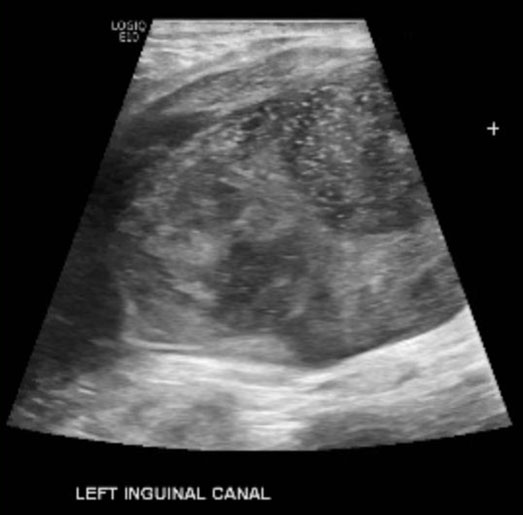

Axial computed tomography (CT) imaging through the left groin demonstrated a small low-density nodule in the inguinal canal, initially believed to be fluid in a small hernia sack (Figure 1). After rapid clinical growth, an ultrasound image of the same mass demonstrated a solid lesion having significantly grown as the preceding CT (Figure 2). A fine-needle aspiration was performed with inconclusive results. Due to further enlargement, an excisional biopsy was performed with a partial excision after which the patient developed wound complications. The post-operative infection was treated with debridement and re-opening of the initial incision with later closure.

Figure 2: Grayscale ultrasonography through the left groin shows rapid interval enlargement of the largely hypoechoic, heterogenous mass with increasing peritumoral fluid and internal microcalcifications.